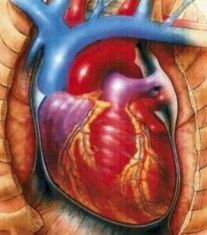

heart-16-9-2010

heart-16-9-2010

heart-16-9-2010

heart-16-9-2010